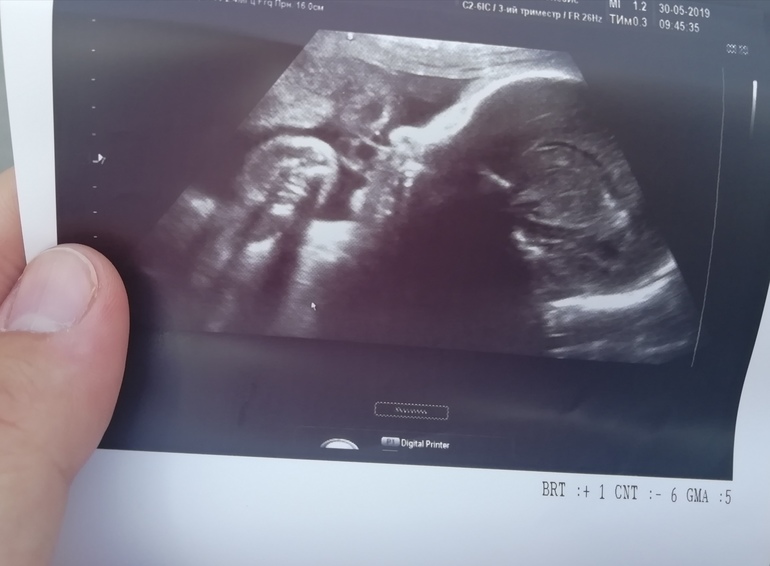

УЗИ, КТГ, доплерВсе хорошо и самое главное, лежим уже головкой вниз, околоплодных вод норма, плацента 1 степени зрелости, вес 2276 гр предположили 🙈хотели сделать 3Д фото, не дал, закрылся полностью и ручками и ножками и фигушки вам, появлюсь на свет-смотрите на здоровье 😂😂😂и вообще крутился только в путь🙈но самое главное все хорошо, осталось немножко и увидимся 😍пол подтвердили мальчик, снова сходу😁а из головы не выходит, а вдруг рожу и там отвалится чей че по пути😂😂😂дали фото 2д

Мне кажется или у нас приличный такой носик🙈😅 девочки, помните вес малышей в 3 скрининг и на какой неделе? У кого в 33 сколько весил? А если уже родились, то с каким??